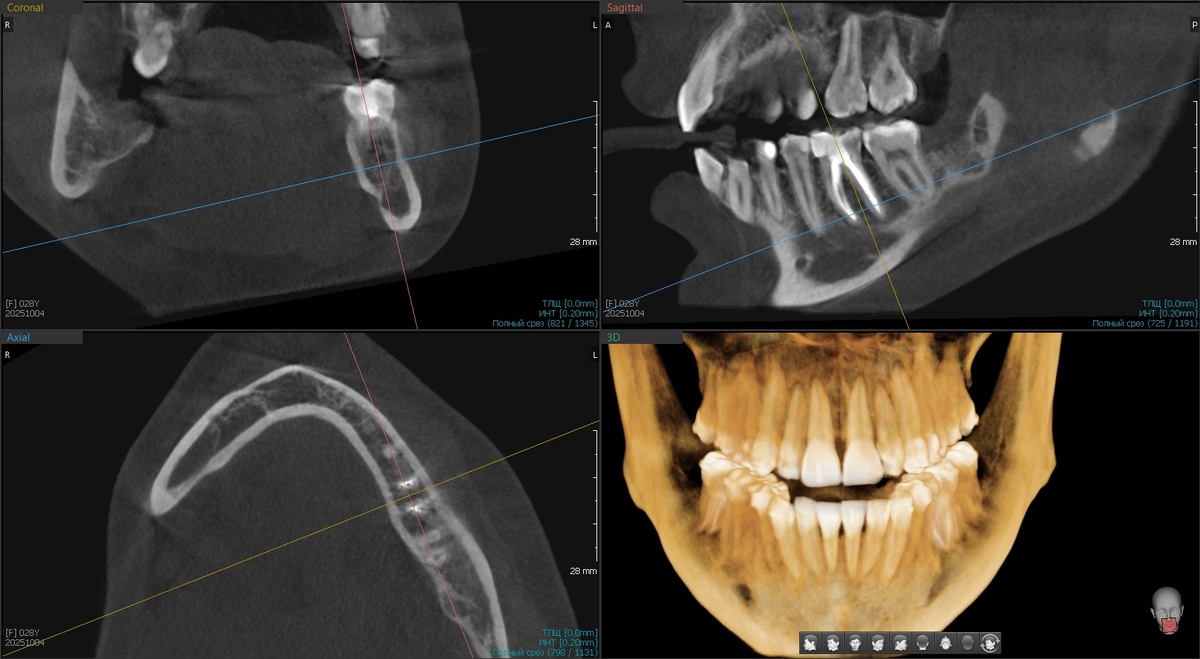

Компьютерная томография показала - Buccal Shelf, практически, отсутствует.

-2

Ширина костной полочки никакая. Попытка установить мини-винты закончились бы предсказуемо - через две недели винты бы выпали, перед этим повредив слизистую оболочку щёк.